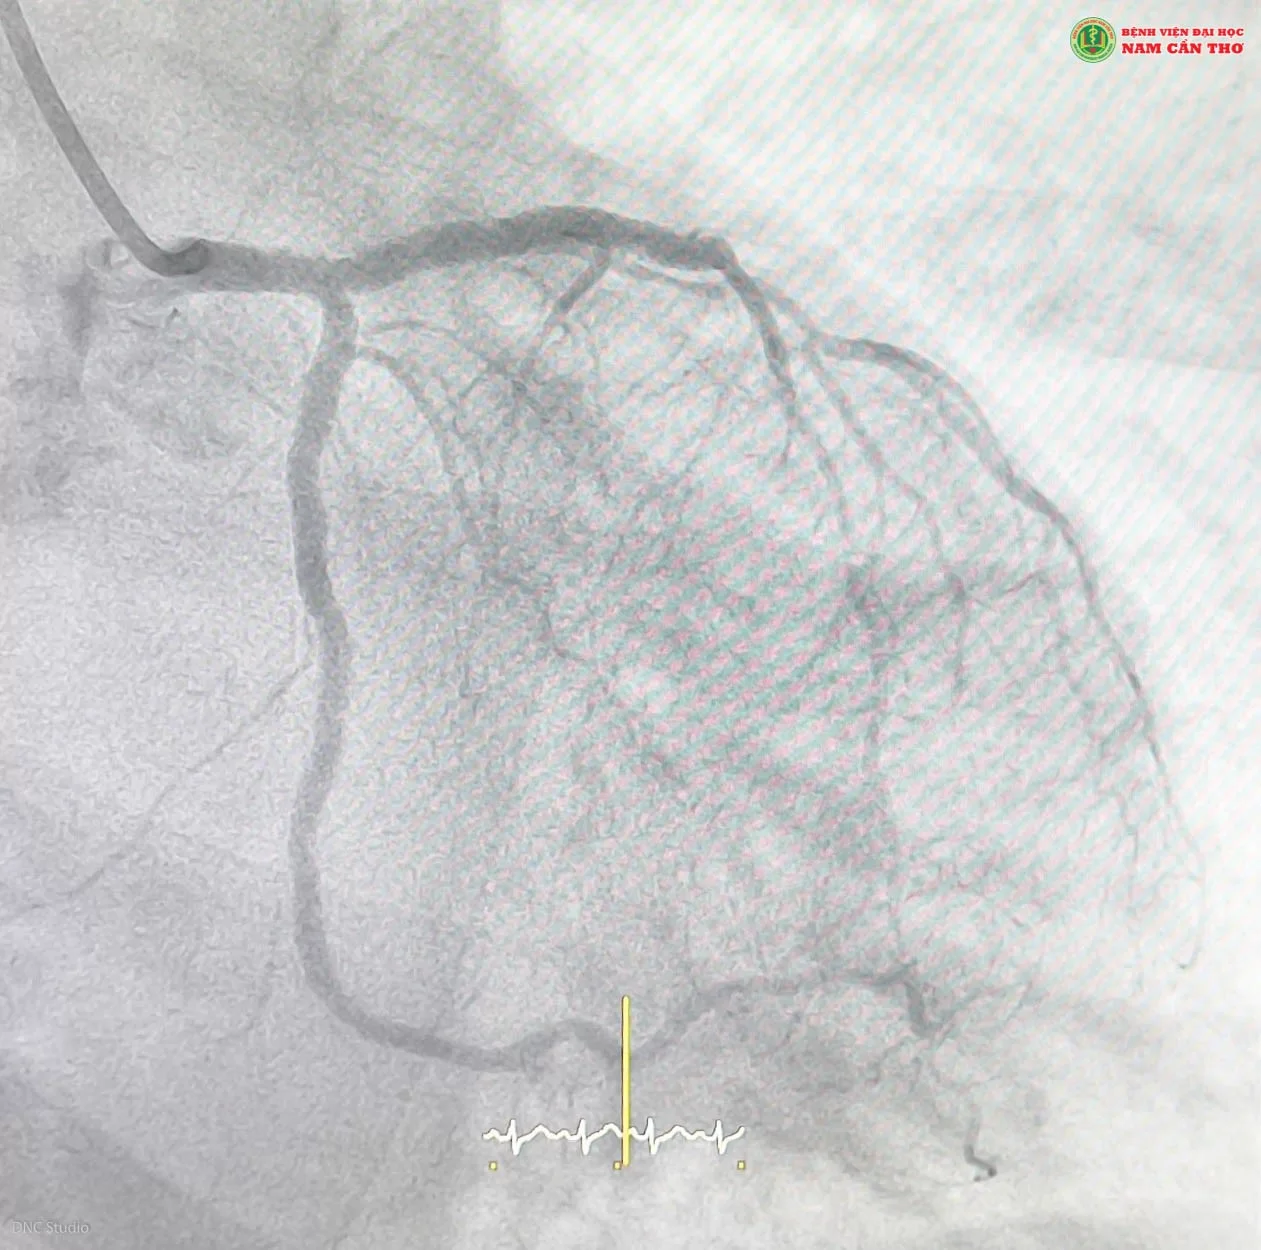

Kết quả tái thông mạch vành của bệnh nhân T.V.P (Ảnh DNC Studio)

Sau khi giải thích cho gia đình hiểu rõ về tình trạng của bệnh nhân. Ekip đã tiến hành can thiệp và sau 90 phút can thiệp, ekip đã cứu sống bệnh nhân trước tình huống nguy hiểm. Sau can thiệp bệnh nhân hết đau ngực, dễ thở hơn, không cần thở oxy mask, sinh hiệu ổn. Tiếp tục theo dõi điều trị tại Khoa Tim mạch và Can thiệp tim mạch, Bệnh viện Đại học Nam Cần Thơ.